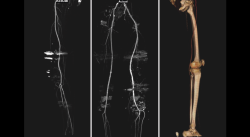

2.5. Afectación vascular

Aunque es rara la afectación de los vasos poplíteos, tanto en las fracturas como en las luxaciones, el estudio con angio-TAC permite el diagnóstico de estas lesiones. La afectación arterial es poco frecuente y la trombosis venosa profunda la lesión más común (Figura 25).

Figura 25. Reconstrucción MIP (proyección de máxima intensidad) de angio-TAC de miembros inferiores: son frecuentes los desplazamientos arteriales de los vasos comprimidos por los fragmentos de las fracturas como en la imagen central. Figura derecha: reconstrucción 3D.